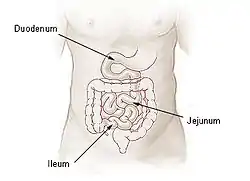

Small intestine | |

The duodenojejunal flexure or duodenojejunal junction, also known as the angle of Treitz,[1][2] is the border between the duodenum and the jejunum.

The ascending portion of the duodenum ascends on the left side of the aorta, as far as the level of the upper border of the second lumbar vertebra. At this point, it turns abruptly forward to merge with the jejunum, forming the duodenojejunal flexure. This forms the beginning of the jejunum.[3] The duodenojejunal flexure is surrounded by the suspensory muscle of the duodenum.[4]: 274 It is retroperitoneal, so is less mobile than the jejunum that comes after it, helping to stabilise the jejunum.[5]